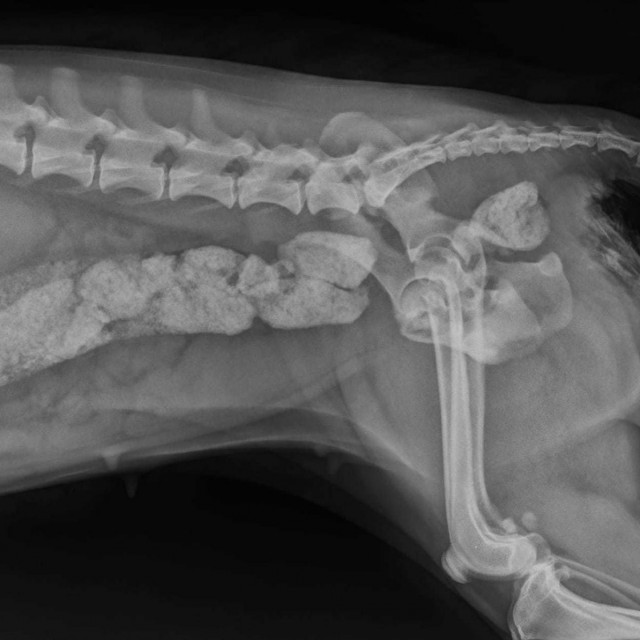

Iz vukovarske veterinarske ambulante Anubis sa svojim su pratiteljima podijelili informacije o jednom takvom psu. Ovaj je mališan neko vrijeme jeo kosti - je li riječ o tome da nije imao što drugo jesti ili da ih je dobivao od vlasnika koji su mislili da je to dobro, ne zna se. No snimka njegovih probavnih organa prilično je rječita.

- Mali pas, puno kostiju i dobijete cijelu kompoziciju u crijevima, koja na žalost često ne ide nigdje bez kirurškog zahvata - napisali su.